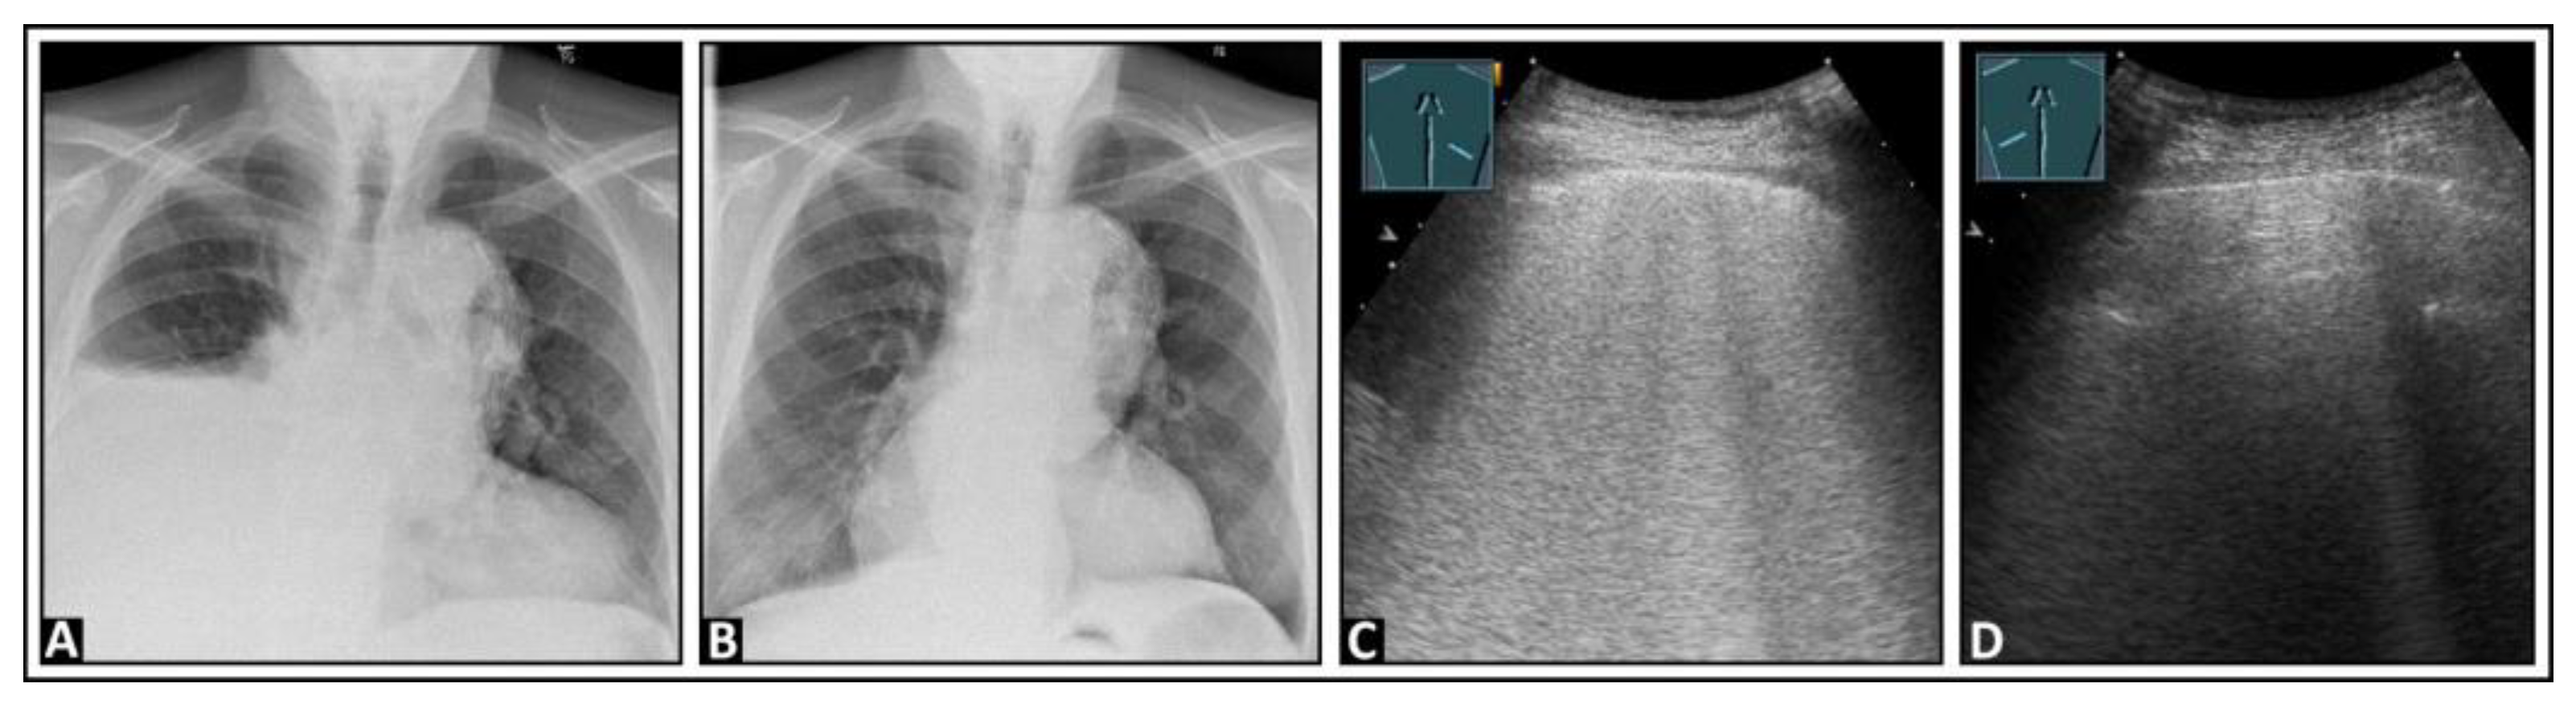

6. Interstitial Lung Disease

7. Other Pathologic Situations

8. Pleural Artifacts with Simultaneous Presence of Consolidation